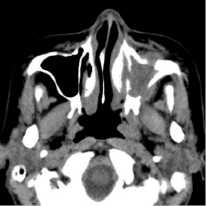

29.09.2016 г. была произведена мультисрезовая спиральная компьютерная томография челюстно-лицевой области. В верхнечелюстной пазухе, передних, средних клетках решетчатого лабиринта и лобной пазухе слева определяется гетерогенное патологическое содержимое, КТ-плотностью от +21,7 ед.Н. до +39,0 ед.Н., с четкими контурами, максимальным размером до 62,0х48,0 мм в поперечнике, на фоне которого визуализируются очажки кальцинации, а также неполностью лизированные костные фрагменты. Определяется остеодеструкция нижних отделов всех стенок верхнечелюстной пазухи, клеток решетчатой кости, а также передних отделов медиальной стенки орбиты слева. Остеодеструкция носит смешанный характер за счет инфильтративного остеолизиса и атрофии от давления. Частично сохранные стенки верхнечелюстной пазухи слева утолщены, в сравнении с контрлатеральной стороной (остеопериостоз). Через вышеперечисленные костные дефекты патологическое содержимое распространяется в одноименную полость носа, мягкие ткани щечной области, ретромаксилярное пространство, а также в передне-медиальные отделы орбиты. Носовая перегородка искривлена вправо. Носоглотка и другие околоносовые пазухи без особенностей.

Заключение: КТ-данные за гетерогенное остеодеструктивное объемное образование околоносовых пазух слева с интраорбитальным распространением (новообразование?). Описанные изменения представлены на рис. 1-2.

Рис. 1. На аксиальном КТ-срезе определяется объемное образование, вызывающее остеодеструкцию по смешанному типу всех стенок верхнечелюстной пазухи слева